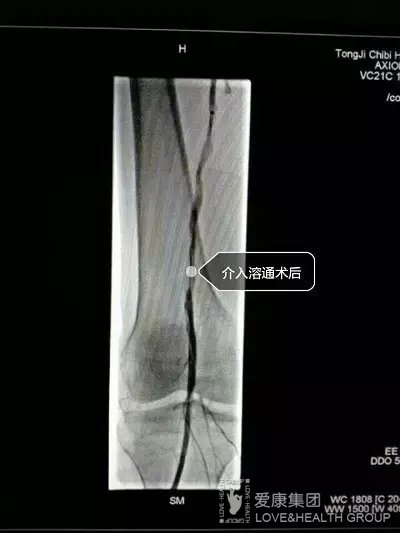

3月8日下午,同濟(jì)赤壁醫(yī)院介入科連續(xù)接診了兩例下肢股動(dòng)脈長(zhǎng)段栓塞的中老年病人。兩人自訴患肢缺血跛行并疼痛多年,都曾為此輾轉(zhuǎn)多家醫(yī)院求治未果。近期疼痛加劇,無法忍受而來院就診。經(jīng)檢查發(fā)現(xiàn)患肢皮膚發(fā)暗、肢端發(fā)涼,再不及時(shí)診治將會(huì)導(dǎo)致肢體缺血壞死。介入科術(shù)前會(huì)診并精心準(zhǔn)備后,分別為兩名患者進(jìn)行了精準(zhǔn)、細(xì)致的介入手術(shù)治療,患者下肢不適癥狀立馬緩解,皮膚由蒼白恢復(fù)紅潤(rùn),缺血冰涼的患肢變溫暖?;颊呒凹覍儆芍愿锌狠氜D(zhuǎn)四方求治,花費(fèi)了大量金錢和精力,想不到家門口同濟(jì)赤壁醫(yī)院有如此獨(dú)到的醫(yī)療技術(shù),省時(shí)、省力又省錢,真是太方便了!出院后一定要廣而告之,讓更多親朋好友知曉這個(gè)好消息。

據(jù)該科涂敬國主任介紹,介入科自成立以來,依托頂尖設(shè)備及同濟(jì)醫(yī)院技術(shù)優(yōu)勢(shì),不斷拓展業(yè)務(wù)范圍,探索更多未知領(lǐng)域,介入診療技術(shù)得到了迅速提升,多項(xiàng)手術(shù)引領(lǐng)開拓區(qū)域空白。其中血管栓塞介入溶通術(shù)已成熟開展多例,“四兩拔千斤”,切切實(shí)實(shí)體現(xiàn)了介入微創(chuàng)技術(shù)的強(qiáng)大生機(jī)和活力,解除了許多疑難病患的痛苦,使“患者至上”的核心價(jià)值觀得到了更好的發(fā)揚(yáng)和傳承。